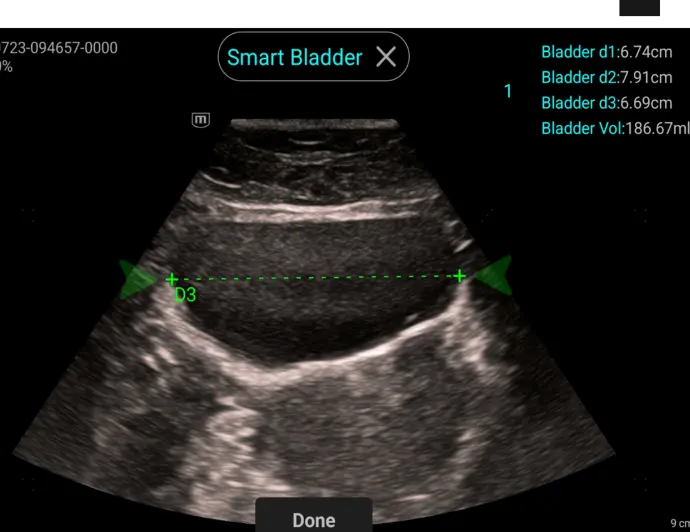

Smart Bladder

Aвтоматично измерване на 3те размера и калкулиране на обема на пикочния мехур

Клинични снимки